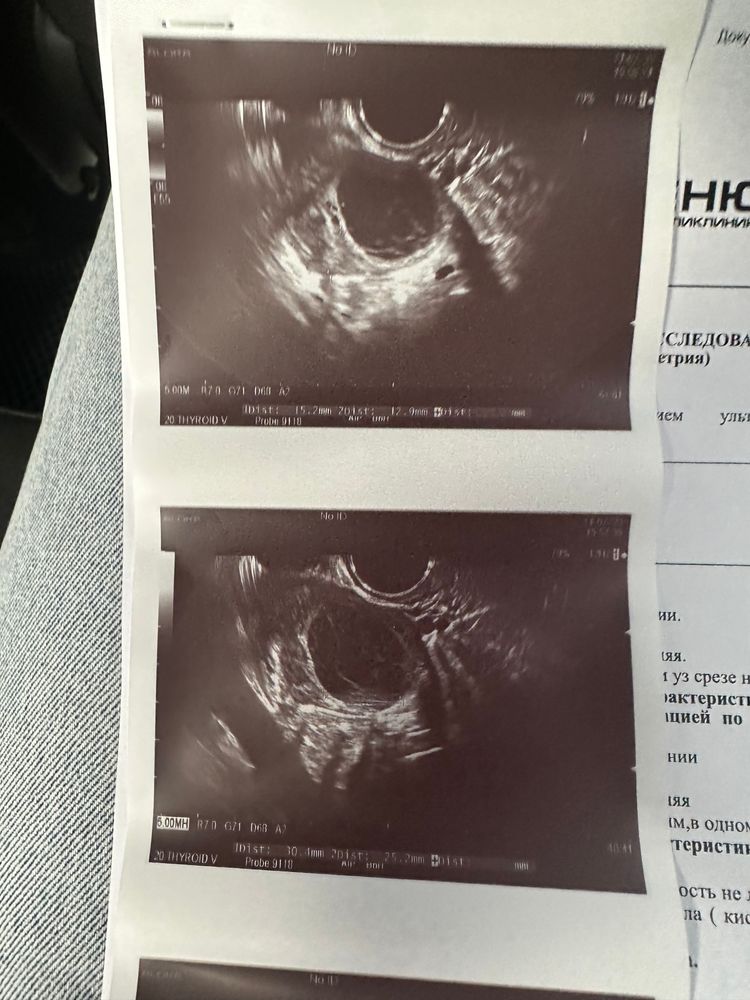

У Вас там целых два ЖТ! Стимуляция была? Беременность возможна, конечно.